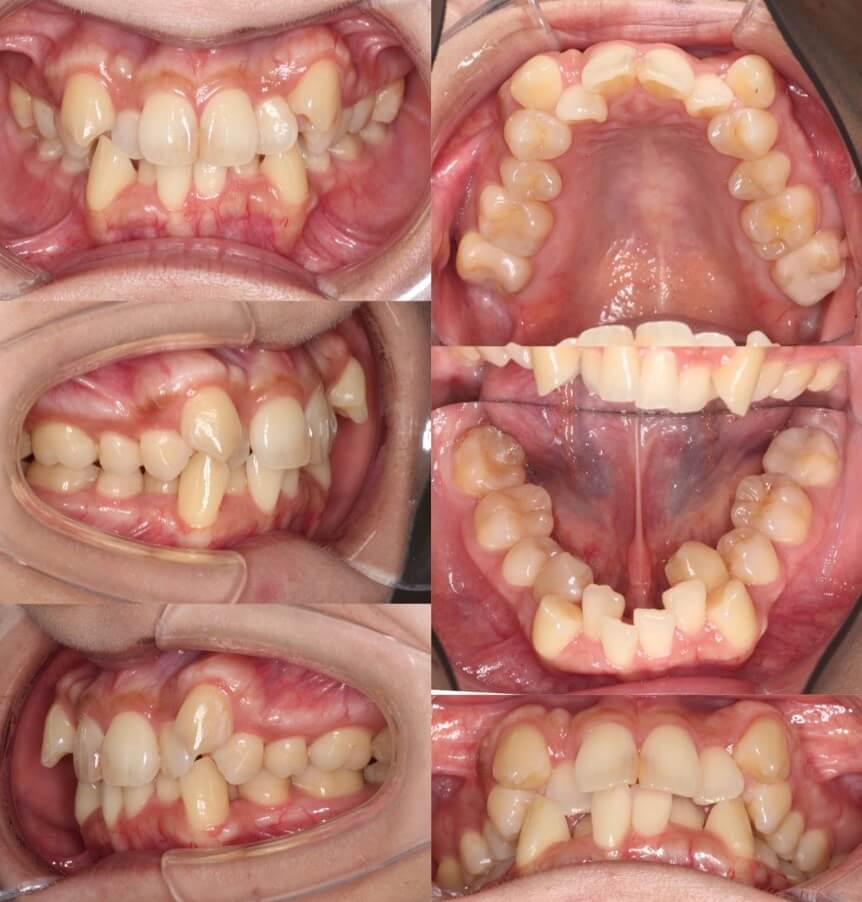

42歳女性・重度叢生・マウスピース装置

ミドルエイジの矯正治療では、できる限り抜歯を併用しないのですが、このように重度のがたつきがある場合は、抜歯を併用します。

<症例概要>

主訴:がたつき

年齢・性別:40代女性

住まい:千葉県佐倉市

症状:叢生・下顎右辺・右II級

抜歯:上左右4番・左下4番(計3本)

治療方針:抜歯空隙閉鎖

治療装置:マウスピース型矯正装置(アライナー装置)

治療期間:2年0か月

アライナー枚数:34+27-14ステージ

リテーナー:上フィックスタイプ+プレートタイプ

治療費用:990,000(税込)

代表的副作用:痛み・治療後の後戻り・歯根吸収・歯髄壊死・歯肉退縮

▶︎その他の副作用

【治療シミュレーション】

上の抜歯空隙に、ゆっくりと確実に犬歯を移動させます。